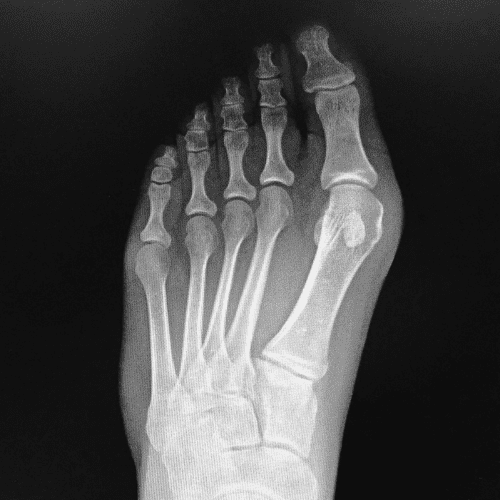

At Rapid City Medical Center, Dr. Jennifer Ryder provides expert podiatric care for patients of all ages, helping them stay active, comfortable, and pain-free. As a board-certified specialist with deep roots in the Black Hills, Dr. Ryder treats a wide range of foot, ankle, and lower leg conditions with a thoughtful, patient-first approach. Whether you’re dealing with heel pain, bunions, plantar fasciitis, diabetic foot concerns, or a sports-related injury, she offers personalized treatment plans that combine advanced diagnostics, surgical expertise, and targeted rehabilitation.